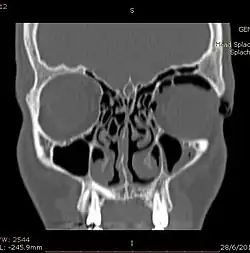

![]() | |

| Woman with preorbital swelling in orbital emphysema shown in CT scans | |

Computed tomography (CT)

Computed tomography is effective and sensitive in the diagnosis of orbital emphysema,[3][37] as it can confirm the anatomical location and size of air, bony defects, indentation of the eyeball, and the condition of the optic nerve, as well as the presence of any extraocular muscle entrapment and herniation of preorbital fat into the sinus cavities.[3][15][38] The location of the orbital emphysema is present near the site of the fracture.[1][3] The scans are usually taken along the transverse plane. Transverse images allow the evaluation of fractures in medial and lateral orbital walls. By reformatting these transverse images or taking coronal images, the examination of orbital floor and roof is permitted. Helical scanning is preferred as it has a lower imaging time and radiation dose comparing to conventional scanning, especially when reforming transverse helical scans into coronal images.[3] The staging of orbital emphysema can then be determined with visual acuity examination and ophthalmoscopy.[6] A disadvantage of using a CT scan is that when detecting air after orbital trauma, the presence of a wooden foreign object can give a false positive result of orbital emphysema. The wooden object can mimic the presence of orbital emphysema. Therefore, patients’ medical history is crucial in making the correct diagnosis.[3]